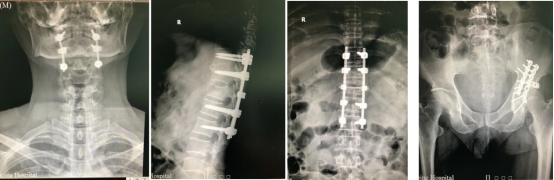

图2 患者周某术前影像学资料

9.3日确定手术方案、手术时间、手术人员等安排;拟9.4给患者周某进行“颈2骨折切开复位椎弓根钉系统内固定术”,拟9.5日给患者李某行“髋臼骨折切开复位内固定、胸12骨折切开复位内固定术”。

9.4日患者周某手术顺利完成;9.5日患者李某手术顺利完成。

9.7日复查术后X片,患者李某可在床上自由翻身,患者周某恢复正常活动。